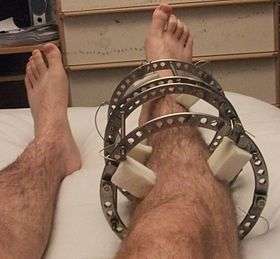

The following case study illustrates the Ilizarov apparatus treatment procedure for a fractured limb. The photographs are of the same patient during the course of treatment.

X-Ray of fracture and initial external fixator applied within 24 hours of patient's admission to hospital Front-left view of the Ilizarov apparatus treating a fractured tibia and fibula. The patient suffered an open fracture. It is located slightly above black metal ring. Photographs 1 through 4 are taken four weeks following the fracture and two weeks following the installation of the Ilizarov apparatus.

Front-left view of the Ilizarov apparatus treating a fractured tibia and fibula. The patient suffered an open fracture. It is located slightly above black metal ring. Photographs 1 through 4 are taken four weeks following the fracture and two weeks following the installation of the Ilizarov apparatus. Front (top) view with a view of the healthy leg. The patient is lying on his stomach.